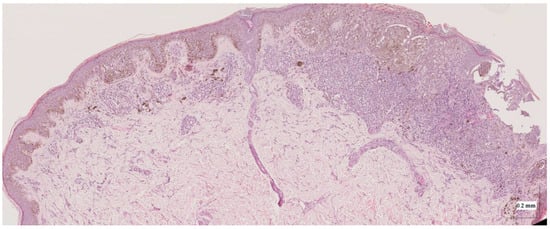

| Superficial spreading melanoma (SSM) Case 1 | Localization: right anterior arm |

![]() | ![]() |

| Superficial spreading melanoma (SSM) Case 2 | Localization: right forefoot (right ankle) |